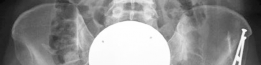

Radiographic assessment must be exhaustive. A standardized anteroposterior (AP) radiograph of the pelvis, centered over the symphysis pubis with neutral pelvic tilt and rotation, is mandatory. On this view, the LCEA, Tönnis roof inclination angle, and extrusion index are calculated. For instance, an LCEA of 18° and a roof inclination of 20° confirm severe lateral and superior uncoverage. A false profile view of the Lequesne and de Sèze is critical for assessing anterior coverage (anterior center-edge angle) and anterior joint space. Dunn 45° and 90° views, or a cross-table lateral, are utilized to evaluate the femoral head-neck junction for CAM morphology.

Advanced imaging is non-negotiable in the revision setting. A high-resolution MRI or MR arthrogram of the hip is required to assess the articular cartilage, the integrity of the ligamentum teres, and the state of the remaining labrum or capsular scar tissue. Anterolateral loss of joint cartilage is a frequent finding in dysplastic hips post-labral resection. Furthermore, a CT scan or MRI utilizing torsional sequences from the hip through the knee is essential to quantify femoral version. A measured femoral anteversion of 36° dictates that a derotational femoral osteotomy (DFO) must be incorporated into the surgical plan to restore normal biomechanics and prevent recurrent anterior subluxation post-operatively.

Patient positioning depends on the planned concomitant procedures. If an isolated SHD with a proximal femoral derotation osteotomy is planned, the patient is placed in the lateral decubitus position on a radiolucent table, utilizing a beanbag and rigid pelvic positioners. The leg must be draped free to allow full manipulation. However, if a Periacetabular Osteotomy (PAO) is required to correct the acetabular dysplasia (e.g., LCEA of 18°), the patient is typically positioned supine or in a "floppy lateral" position. The floppy lateral allows the surgeon to roll the patient backward to perform the anterior approaches required for the PAO after the SHD and femoral work are completed. Fluoroscopy must be easily accessible and unimpeded in all planes.